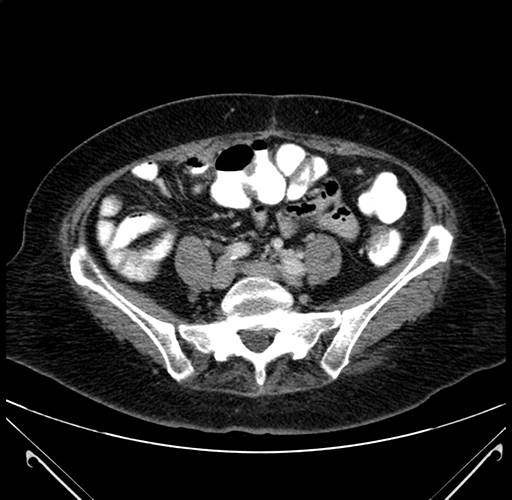

Pre-Chemo: Axial Venous

Axial Venous